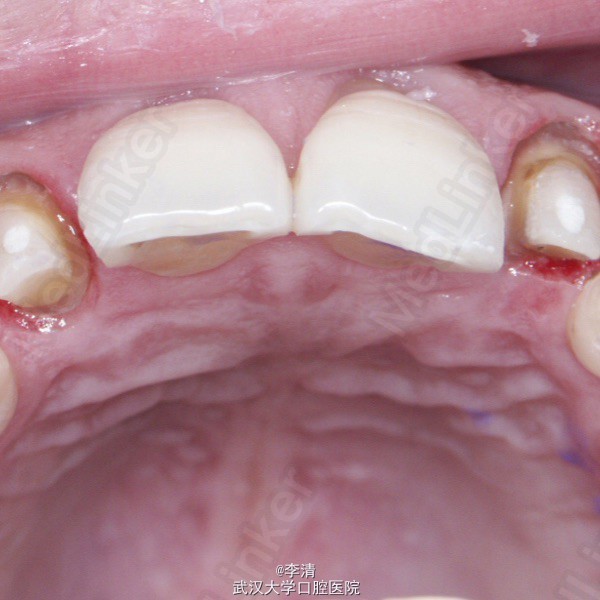

诊断 处理

侧切牙残根 行纤维桩,铝瓷全瓷冠修复